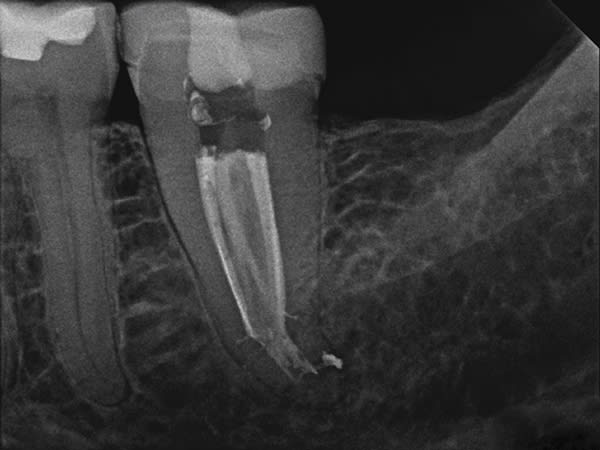

A C-shaped molar root canal can cause even seasoned clinicians to question whether to perform treatment in a one- or two-visit procedure. Tortuous anatomy and unusual root complexities make it difficult to clear all the tissue from the root canal system. Clinicians often opt for sonic or ultrasonic irrigation and a two-visit procedure to assure a positive clinical outcome. In this case, GentleWave® Procedure Multisonic Ultracleaning® technology (Sonendo, sonendo.com) was used to treat irreversible pulpitis in a C-shaped lower second molar, which is often difficult to address. After administration of anesthesia, and with the use of a dental microscope (Leica M320, Leica Microsystems, leica-microsystems.com), conservative straight line access was achieved, and three canals were located, measured, and instrumented. The GentleWave Platform was then built onto the tooth, the Procedure Instrument attached to the GentleWave Console, and the GentleWave Technology finished the procedure. Eight minutes later, the platform was removed, the canals dried, and the canal system filled. Upon completion of the GentleWave Procedure and warm vertical obturation the results were astonishing as evidenced in the final radiograph.

Endodontic challenges such as a C-shaped molar root canal can be treated successfully in one visit with minimal instrumentation and the GentleWave Procedure.